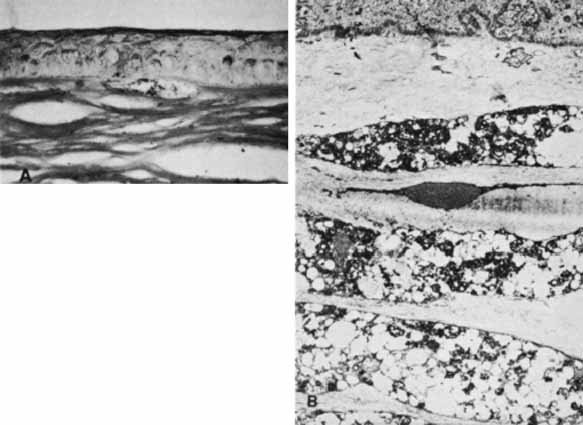

With time, a fresh endothelium will resurface the posterior cornea and synthesize a new basement membrane, filling the dehiscence and accentuating the edges of the tear. After the corneal edema resolves, the edges of the break will appear as rounded, glassy ridges protruding from the posterior cornea readily apparent under retroillumination. In some instances, one edge of the tear may separate from the stroma and hang into the anterior chamber as a falciform ledge, with its free edge curling anterior to form a scroll (Fig. 9). When two tears occur parallel to each other, the edge of Descemet's membrane between the tears may curl toward each other. This strip of Descemet's may then disassociate from the overlying stroma, resulting in a glassy strand across the concavity of the posterior cornea. In this circumstance, the newly laid basement membrane will have a beaten-metal, guttate appearance.

Fig. 9 Histopathology of healed tears in Descemet's membrane from congenital glaucoma. A. Regenerating corneal endothelium has produced new basement membrane in the bed of the tear and over each edge (arrows) of the tear. B. Main figure demonstrates one edge of the tear in Descemet's membrane, which has separated from the overlying stroma and coiled anteriorly like a watch spring. Regenerated basement membrane has encased this and formed a prominent ledge. Inset. Other edge of the tear, in which regenerated basement membrane forms a ridge protruding into the anterior chamber. (Waring GO, Laibson PR, Rodrigues MM: Clinical and pathologic alterations of Descemet's membrane: With emphasis on endothelial metaplasia. Surv Ophthalmol 18:325, 1974)

Histopathologically, the edge of a Descemet tear curls toward the stroma, possibly because of the differential elasticity between the anterior banded and posterior nonbanded layers within Descemet's membrane.67 As the new regenerating endothelium spreads over the edge, it encases the original coiled Descemet's membrane in a thick multilaminar periodic acid-Schiff (PAS)-positive basement membrane (Fig. 9). This new basement membrane forms the clinically evident refractile edge. Within the bed of the tear, the regenerating endothelium lays down an irregular basement membrane with focal excrescences that produce the beaten-metal appearance.